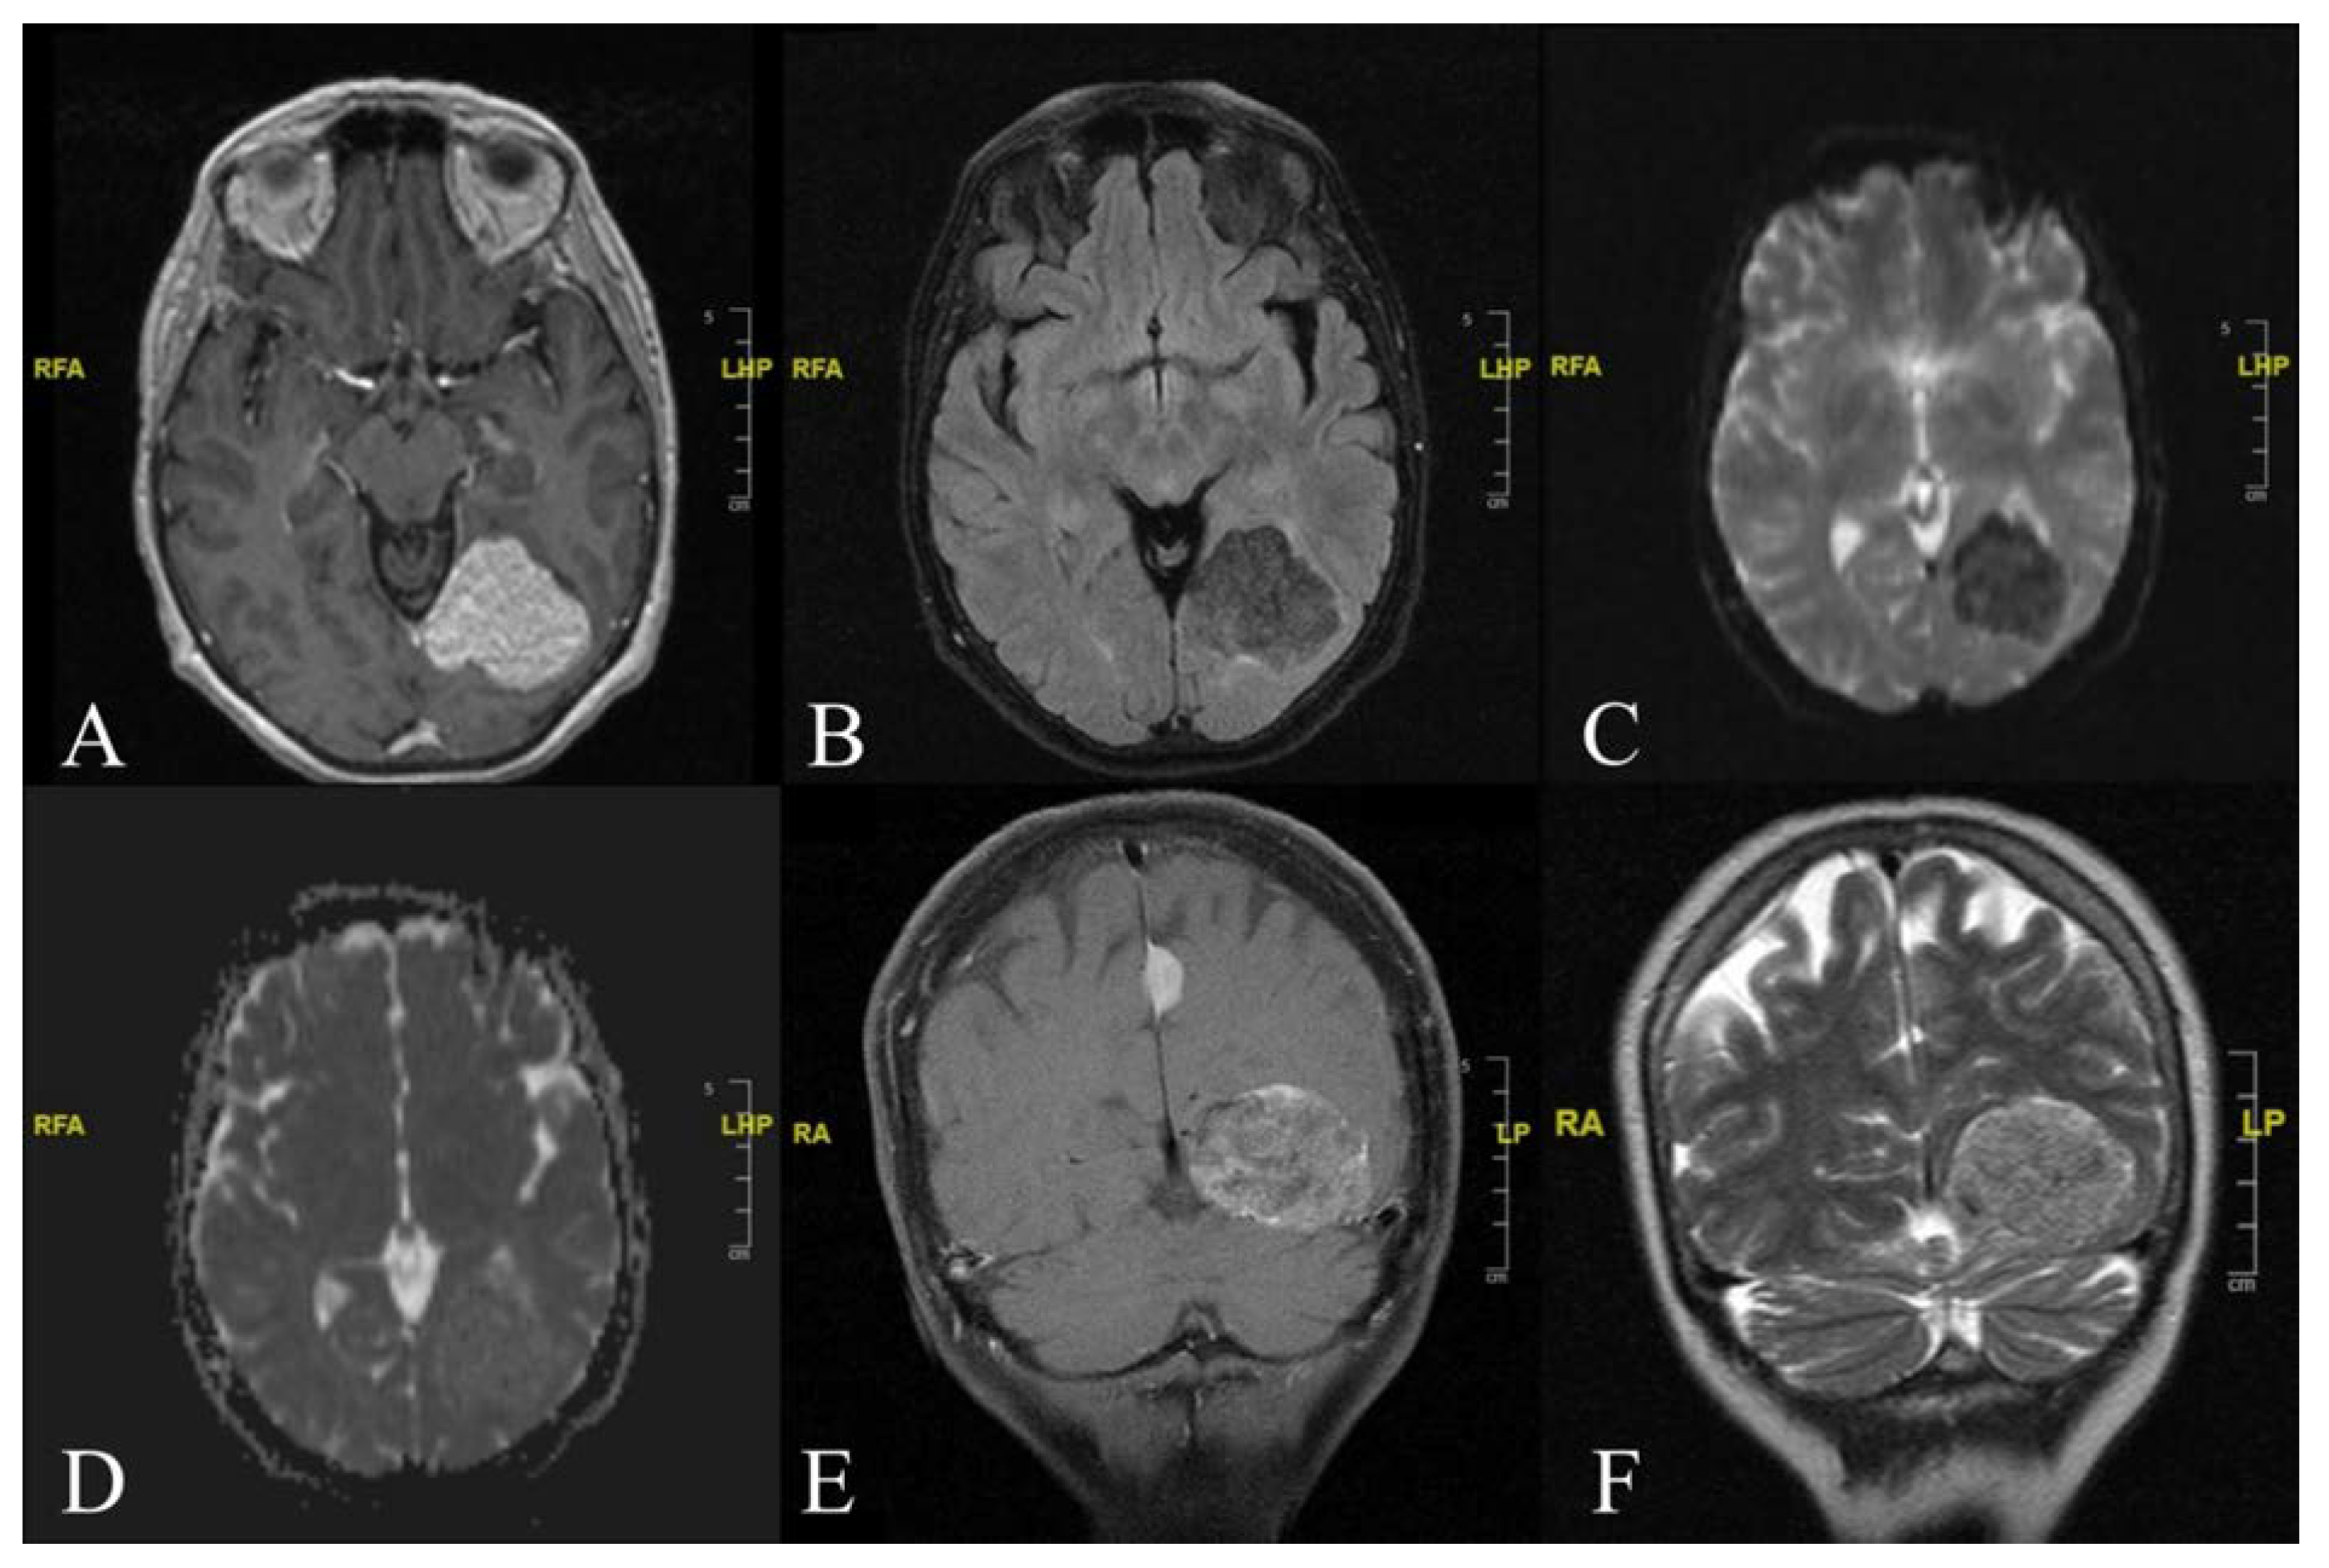

2. Case Report